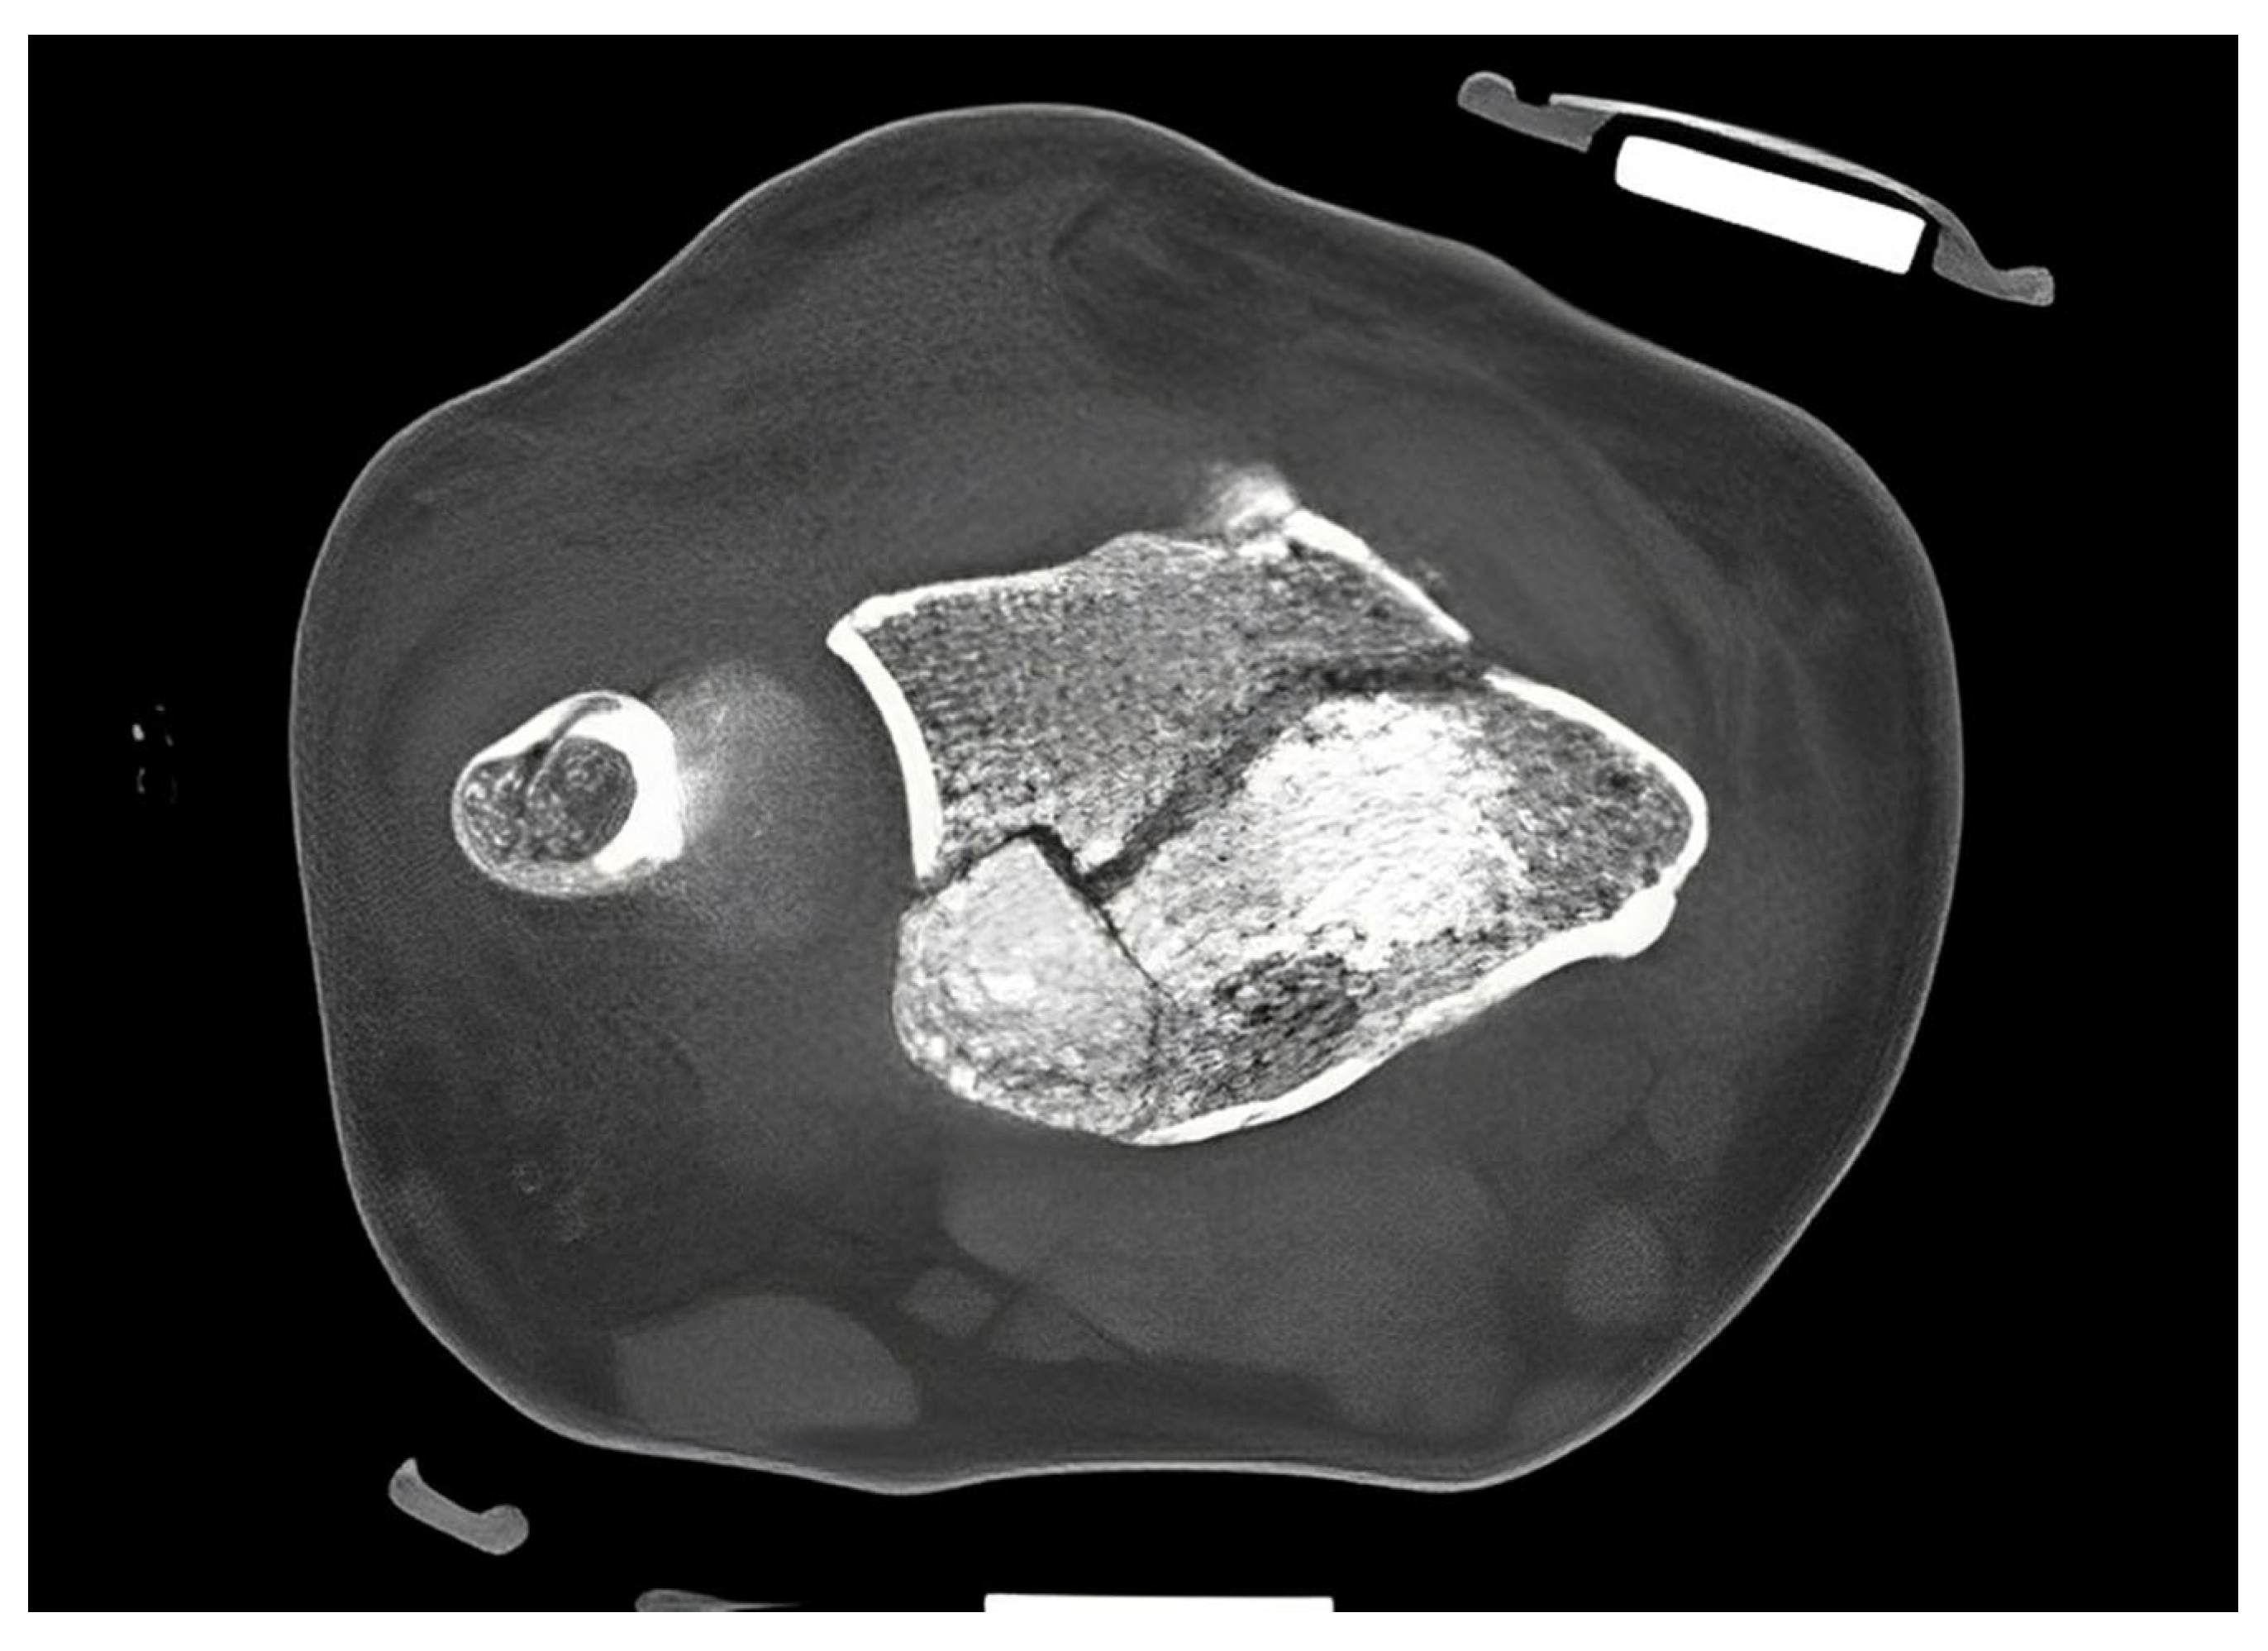

Figure 7.

CT scan of a DRF in transversal view. The use of aluminum-based orthosis does not induce metal artifacts.

The standard treatment approach in our Level I trauma center was not altered by the study protocol, except from the placement of the orthosis. In our approach, we were able to adjust the orthosis used immediately during finger-trap traction and show that there was no increase in secondary dislocations on the radiographic and CT control imaging and, moreover, that diagnostic procedures were in no way restricted when the orthosis was in place. The quality of detail was not limited in any way in the lateral projection, very less in the posteroanterior view (Figure 6A–D). Additionally, the use of the orthosis did not affect the CT scan. As shown in Figure 7, there are no metal artifacts induced by the aluminum splints. Hence, modern orthoses enable comprehensive radiographic diagnostics.